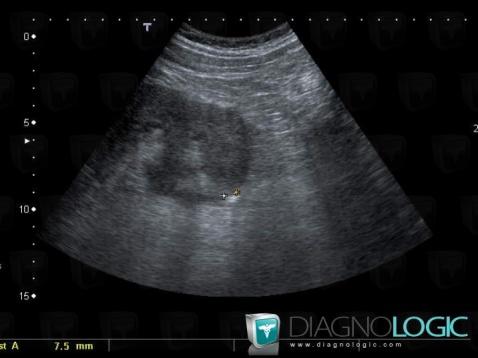

Calculus, Ureter, US

Here is the specific information in the key image above:

- Diagnosis Calculus, Location(s) Ureter, with gamuts Ureteral filling defect